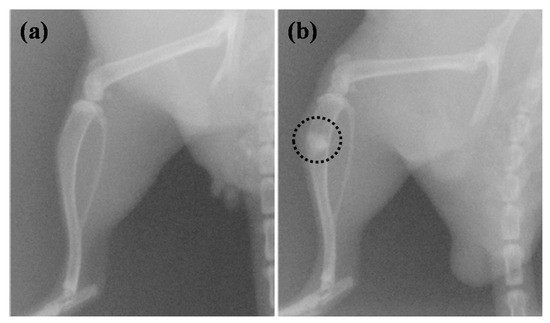

The protocols for animal experiments were reviewed and approved by the Institutional Animal Care and Use Committee for Taipei Medical University under a project identification code of LAC-2015-0073. Twenty-four Sparague-Dawley rats weighing 200–300 g obtained from BioLASCO Co., Ltd. (Taipei, Taiwan) were used in this study. The Sparague-Dawley rats were divided into three groups according to the type of implantation materials, consisting of the testing article (TA; the innovate α-CSH bioceramic) group, commercial product (CP; Merries Uni-Osteo, J.O. Corporation, New Taipei City, Taiwan) group [], and blank group. The implantation procedure was conducted under general anesthesia using isoflurane inhalation. The implantation of approximately 0.1-g powder of α-CSH bioceramic bone graft substitute testing article (n = 4) and commercial predicate material (n = 4) were randomly implanted in the rat’s right hind leg bones after created artificial defects by drilling (diameter: 2 mm and depth: 2 mm), while in the blank group (n = 4), artificially created defects were left without any implanted materials, and radiography was taken immediately after implantation (Figure 1). The animal was sacrificed according to the observational period (3 days and 7 weeks after treatment). A short-term healing observation was used to investigate its early-stage bone healing and inflammatory response.

Figure 1.

The position of the implanted material in the rat’s right hind leg bones: (a) before implantation and (b) after implantation (as indicated by the black dash line).